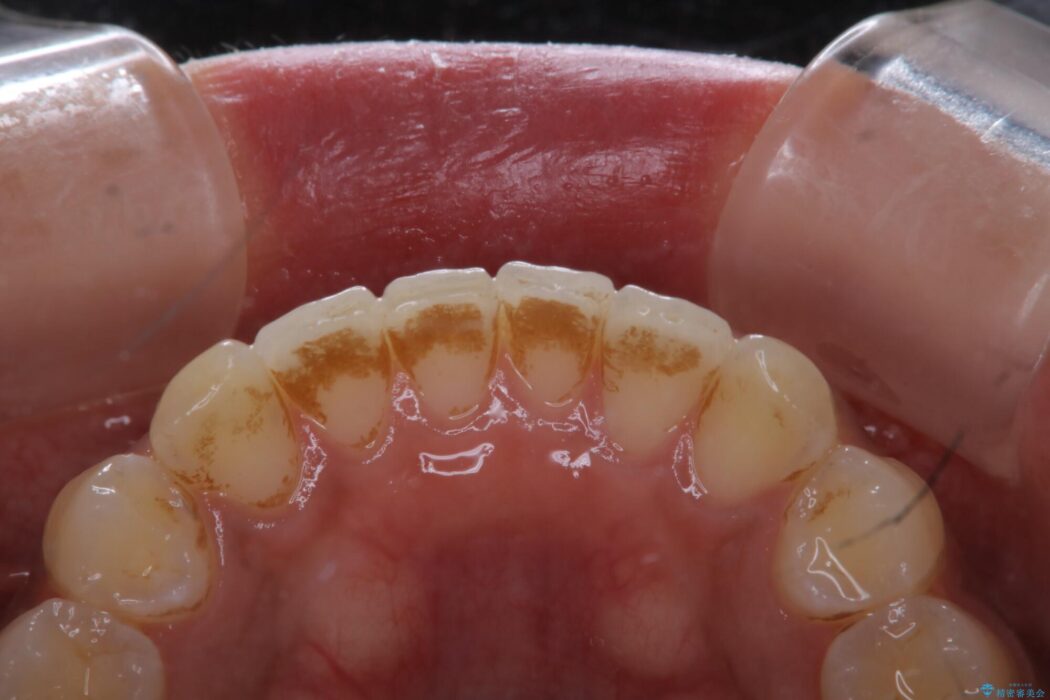

タバコによって付着したステインを綺麗にしたいとのことで来院されました。

ステインがこびりついていたため、PMTC60分コースを行いました。